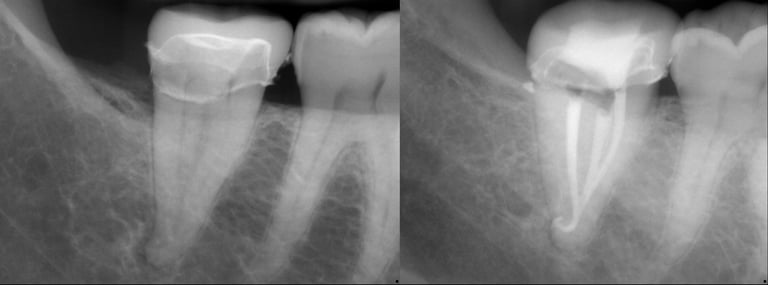

Gallery 1: Initial Cases

Initial Root Canal Cases with preoperative and postoperative radiographs.

#31 RCT

#5 RCT with 3 canals